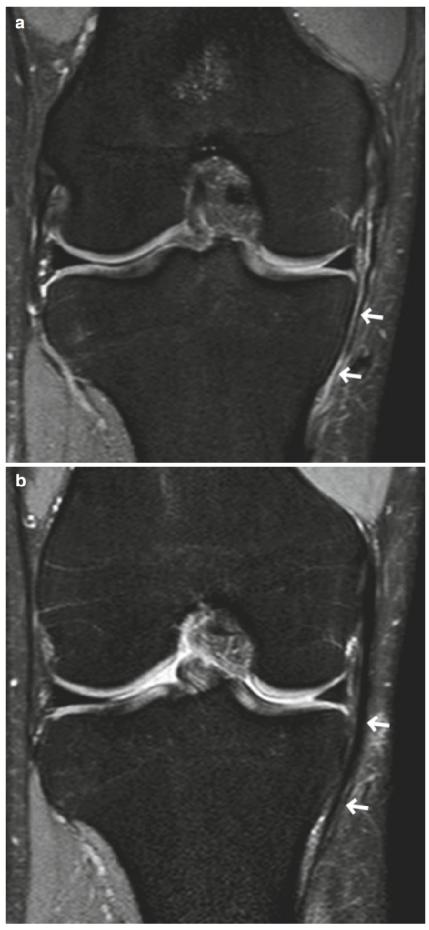

图5.8的2级撕裂(部分撕裂)。一个40多岁的男性。(a)冠状面和(b)轴位FS PDWI显示MCL表层水肿肿胀和不连续(箭头)。水肿的改变也可见于内侧支持带(b中箭头)和股内侧肌(a 中箭头箭头)

图5.11部分撕裂MCL的随访。一个20多岁的女性。冠状面FS PDWI在(a)损伤后即刻扫描;(b )在 7个月后获得。在(a)中,注意到MCL表层的1级撕裂(箭头)。在(b)中,MCL的撕裂部分显示纤维增厚(箭头)